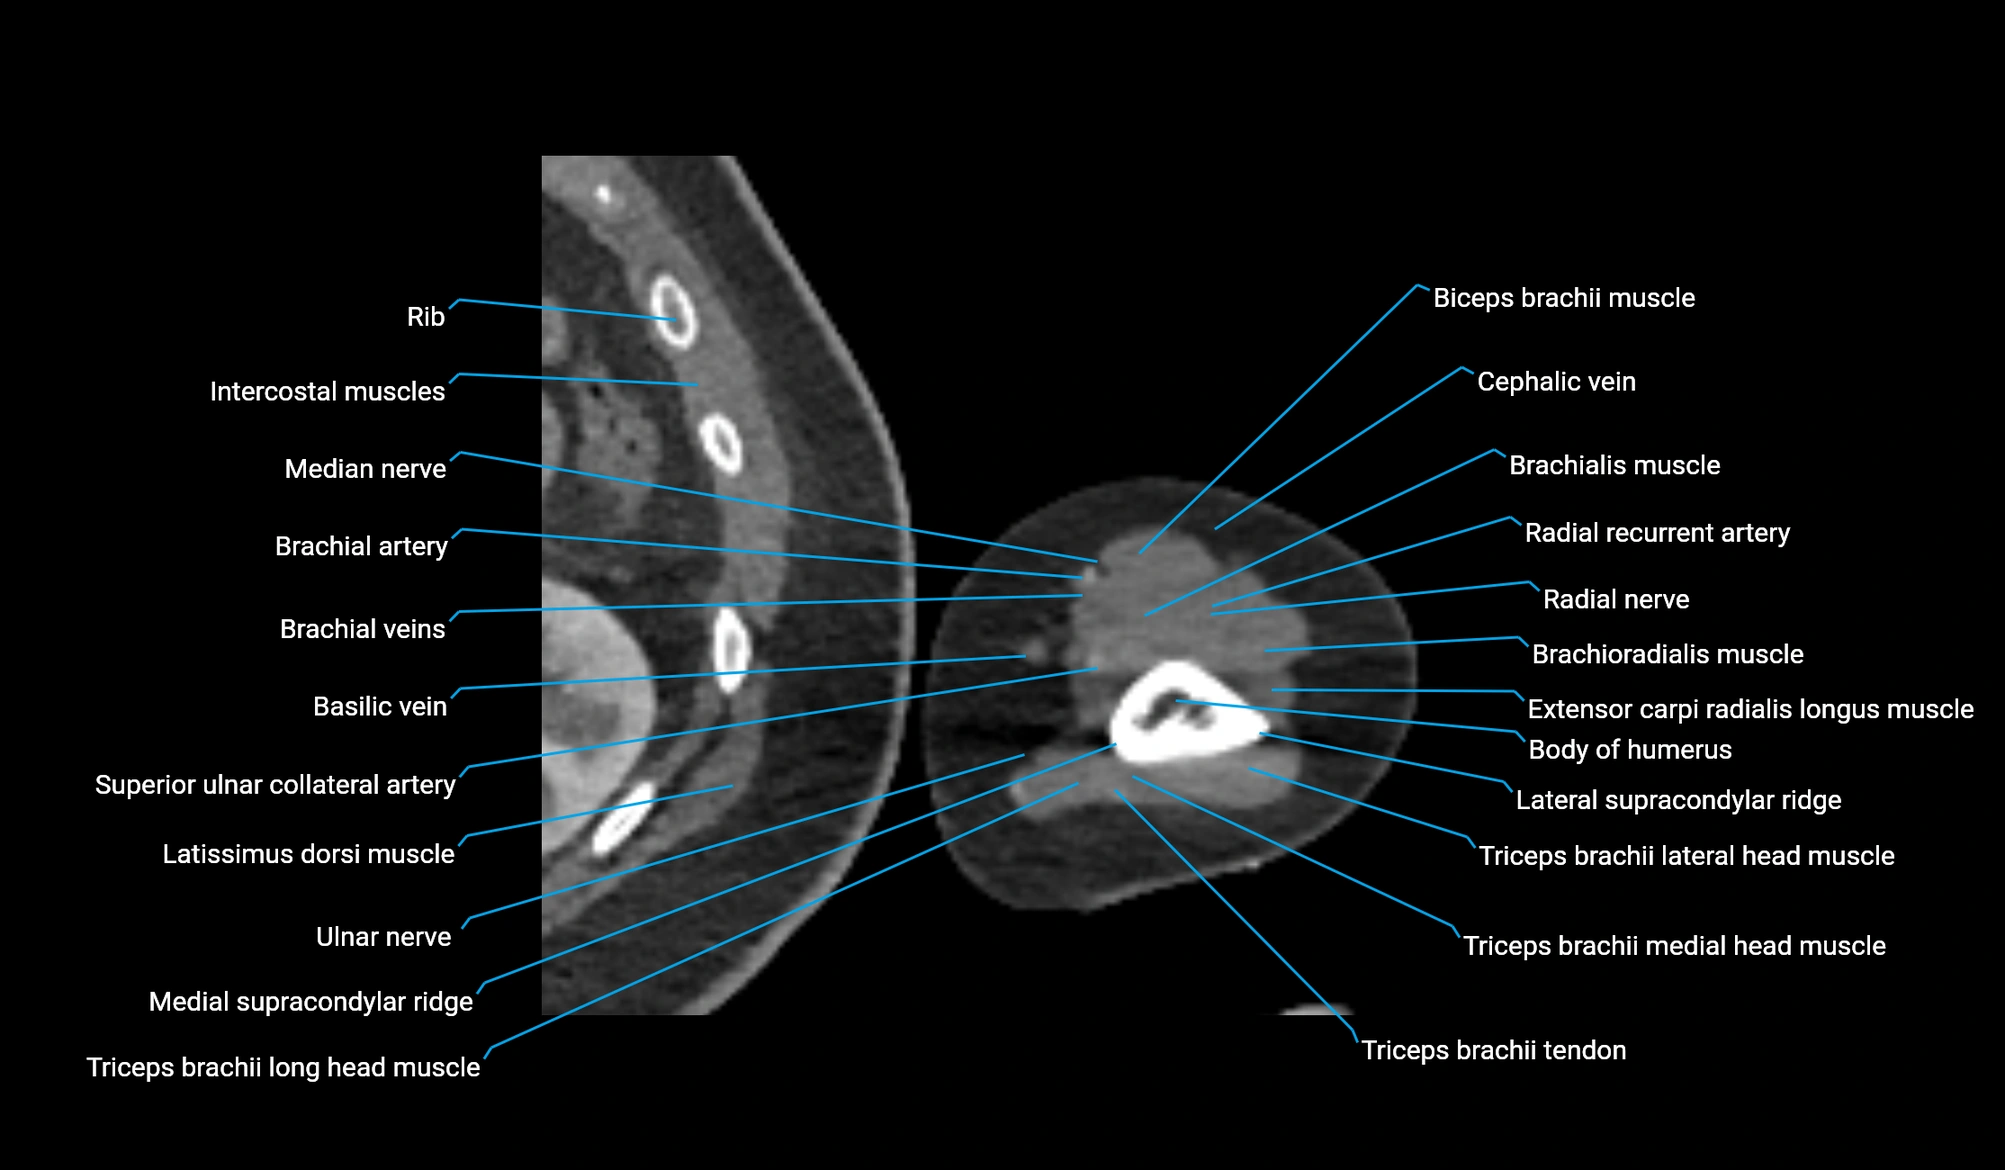

- Biceps brachii muscle

- Brachialis muscle

- Brachioradialis muscle

- Cephalic vein

- Extensor carpi radialis longus muscle

- Lateral supracondylar ridge

- Lateral head of triceps brachii muscle

- Medial head of triceps brachii muscle

- Long head of triceps brachii muscle

- Medial supracondylar ridge

- Median nerve

- Radial nerve

- Radial recurrent artery

- Superior ulnar collateral artery

- Triceps brachii tendon

- Ulnar nerve